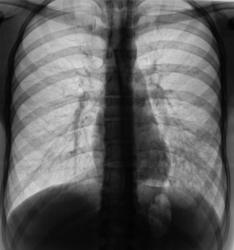

"Красивая" пневмония.

Пациент направлен на исследование врачом терапевтом с диагнозом "пневмония". Клиника пневмонии наличествует.

сегментарная пневмония (8 сегмент) с плевральным выпотом по глвной междолевой щели.